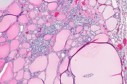

Figure 5.MEN1 syndrome demonstrating goitrous enlargement of thyroid gland with colloid impaction13.

MEN1 syndrome demonstrating               goitrous enlargement of thyroid gland with               colloid impaction13.